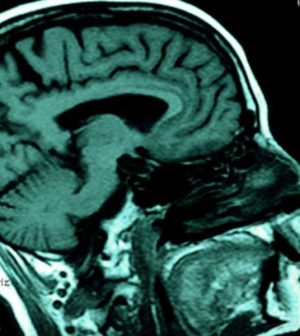

Using electroencephalograms (EEG) to measure brain activity while more than two dozen study participants did mundane attention tasks, the researchers identified brain signals associated with a daydreaming mind.

They found that the participants had increased alpha brain waves in the prefrontal cortex when their thoughts skipped from one topic to another. Alpha waves are slow brain rhythms with frequency ranging from 9 to 14 cycles per second.

They also found that the participants had weaker brain signals known as P3 in the parietal cortex when they weren’t paying attention to the task at hand. The study was published this week in the Proceedings of the National Academy of Sciences.